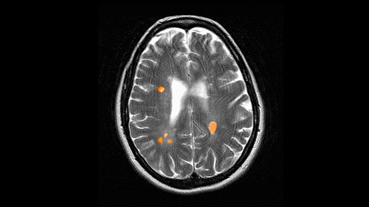

Innovative technologies and alternatives to traditional treatments are transforming the diagnosis and management of neurological conditions. In 2025, NewYork-Presbyterian physicians and surgeons from Columbia and Weill Cornell Medicine used sonication and convection-enhanced delivery to penetrate the blood-brain barrier, validated an adjunctive treatment for subdural hematoma, broadened access to spine surgery, advanced experimental therapies for neurodegenerative diseases, and more. Our specialists have been steadfast in reshaping the fields of neurology and neurosurgery in the pursuit of better patient outcomes and enhanced quality of care.

From cutting-edge research to compassionate patient practice, neurologists and neurosurgeons from Columbia and Weill Cornell Medicine are at the forefront of developing and applying the most advanced approaches to treat debilitating conditions affecting the brain and spine. With a broad range of focus on neurodegenerative and neurovascular disorders to malignant tumors, our innovative and advanced care is leading to new treatment options and enabling patients to achieve the best possible outcomes.